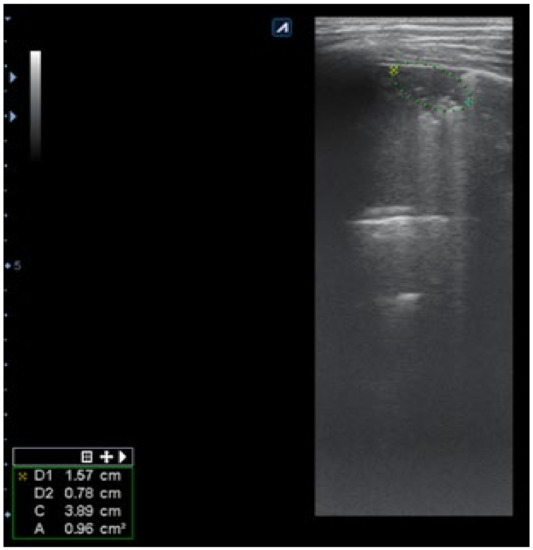

The artefacts used to define the pathological elements were as follows (Table 1): the presence of A lines—normal aspect = 0 points; less than 3 B lines, thin (< 2 mm in width)/intercostal space = 0 points; more than 3 distinctive B lines or 1 coalescent B line = 1 point, quantifying interstitial inflammation or small bronchiectasis (Figure 1) confirmed by CT (Figure 2); more than 2 coalescent B lines = 2 points, suggestive of alveolo-interstitial inflammation or mucus plugging with loss of aeration; either bronchial wall thickening or subpleural consolidation < 1 cm = 3 points, associated with the absence of A lines quantified either as small atelectasis or cystic bronchiectasis with mucus plugging; subpleural lung consolidation > 1 cm, without bronchogram = 4 points; quantified atelectasis (Figure 3)/consolidation with bronchogram = 5 points.

Subpleural consolidation were detected by CT scan (Figure 4) in 33.3% of patients, and confirmed by LUS in 31.5% (Figure 3).

Figure 3. LUS: subpleural consolidation of 1.75 cm/0.78 cm, surface of 0.96 cm2 (score 4), without bronchogram, with adjacent B lines (2 points); A lines also present, examination of left posterior hemithorax.

Figure 4. CT scan of the same patient, with various types of bronchiectasis: (1) cylindrical bronchiectasis with moderate bronchial wall thickening; (2) varicose bronchiectasis; and (3) a round/spiculated consolidation, corresponding to previous LUS consolidation. CT score = 62.